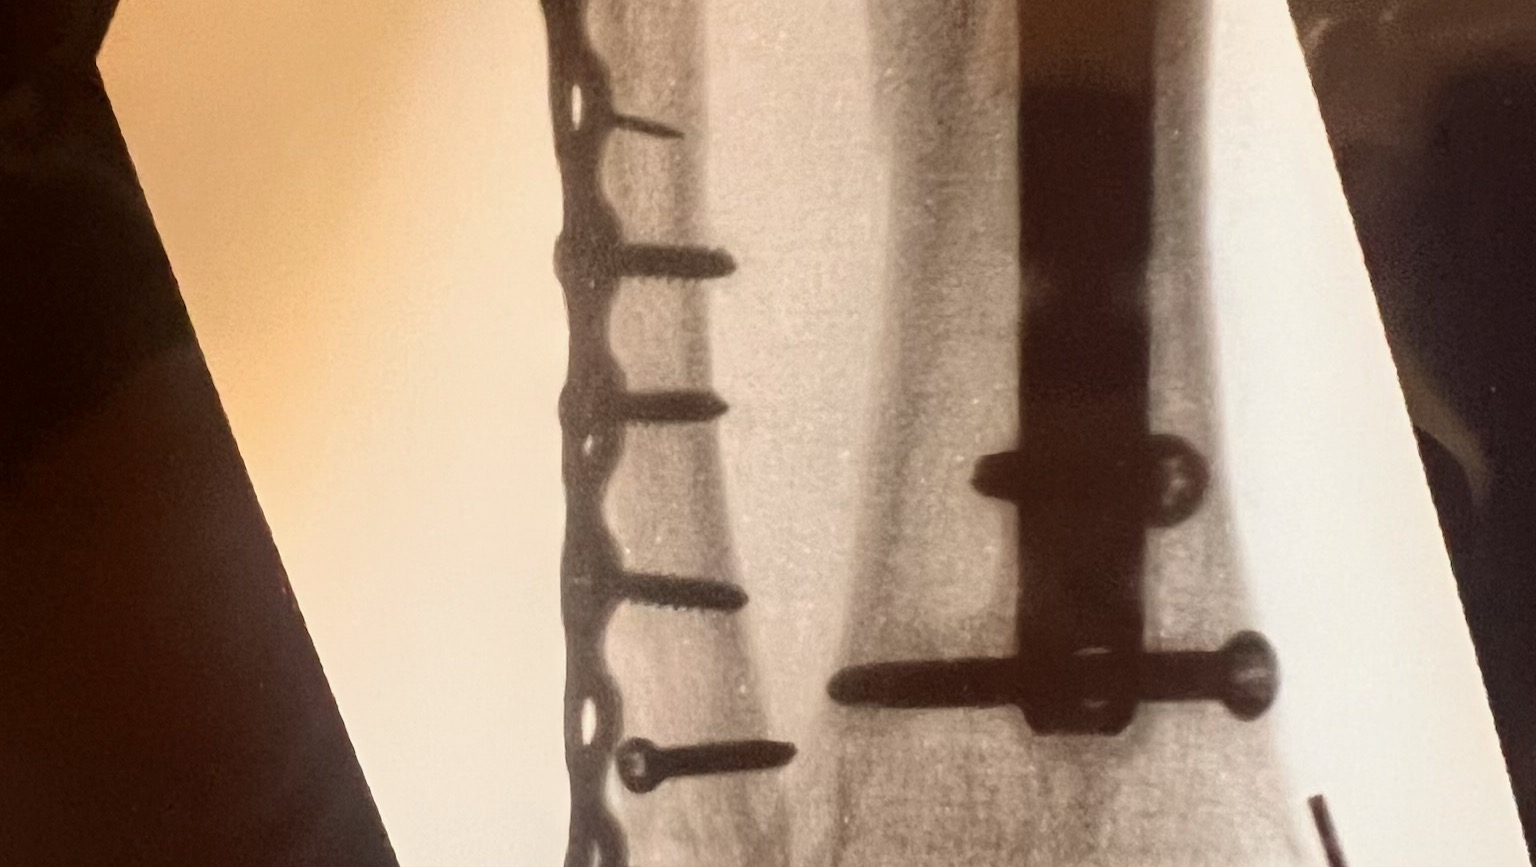

- Hi folks. My name is Sheryl Brooks. CJ is my son and in real need of help. Most of you remember CJ was in a horrible car accident 9 years ago that crushed his right leg. Recently, that leg was fractured again in the worst way possible. He is unable to work. Very stressed, wondering how he is going to support his wife and baby that is due in January. Any help would be appreciated. Prayers are always welcome. Thank you for your support. God bless.